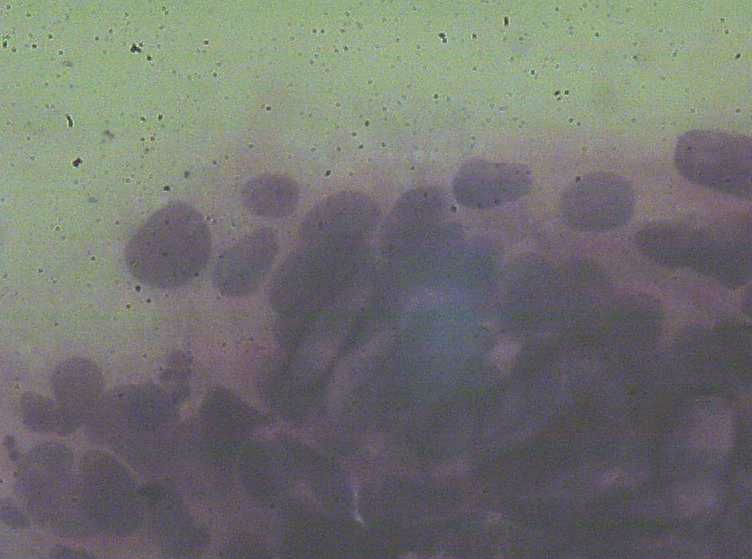

今天把刮片的图片上了,只是拍的图片效果不好。这张刮片的表层鳞状上皮 很好  没有看到不明显的不典型,也没有看到明显的挖空细胞  。那些一堆堆的细胞  不管从形态 和排列上我 觉得都像 腺上皮的  不过有一点不太像就是没有看到明显的核仁 。这张片的组织学  我报了 符合(宫颈)尖锐湿疣伴不典型增生 。建议HPV检测。不知妥否?请大家给予指点